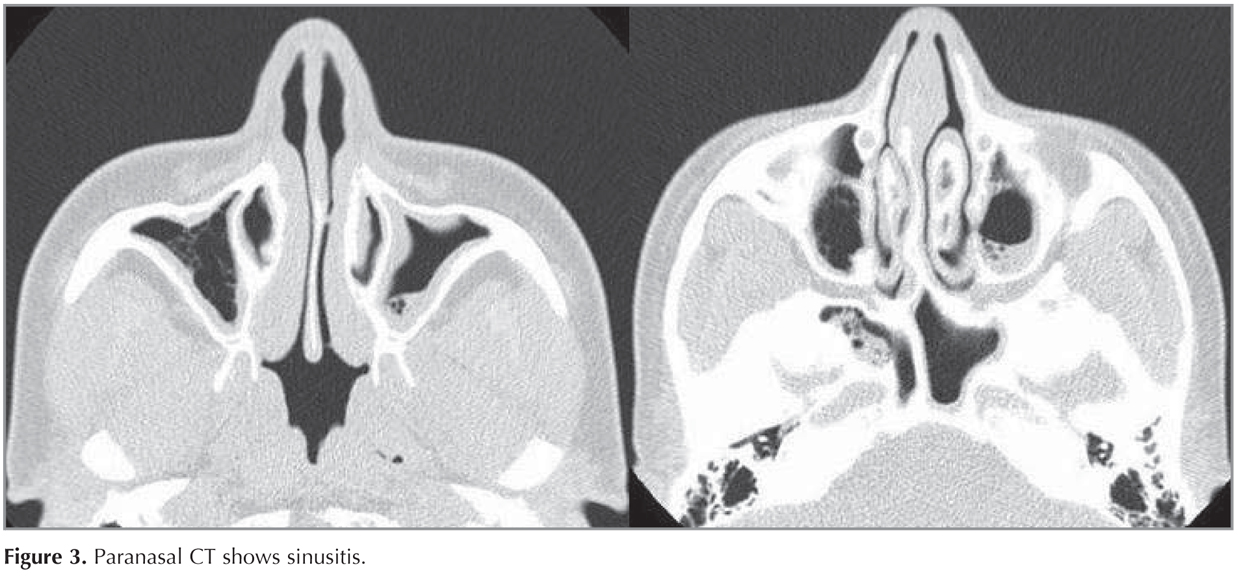

Paranasal CT revealed mucosal thickening as well as soft tissue densities consistent with sinusitis in the mucosa of maxillary, ethmoidal, sphenoidal, and frontal sinuses (Figure 3). Dermatological examination revealed no fungal infection of nails.

Figure 3